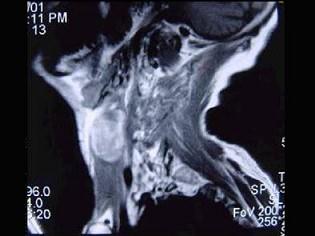

问题 男性,40岁,发现左侧颈部小包块,CT、MRI检查如图所示,请选择最可能的诊断 ( )

选项 A、肿大淋巴结 B、副神经节瘤 C、神经纤维瘤 D、海绵状血管瘤 E、神经鞘瘤

答案 D